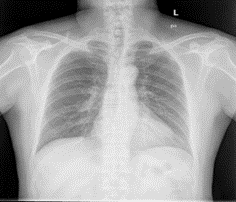

Figure 2: Montgomery data set sample. (a) X-Ray (b) Mask.

Two data sets were used for this experiment. We used the Montgomery data set and the Shenzhen data set. The National Institute of Health and the National Library of Medicine maintain these data sets. In the Montgomery data set, there is a total of 138 images with a size of 4020 * 4892. 58 abnormal images show signs of a wide range of diseases and there are 80 normal cases. Shenzhen X-Ray data set is made up of 662 frontal chest X-Ray with 326 normal cases and 336 abnormal cases. The samples are in PNG format. Images are roughly 3000*3000 in size. Figure 1 and Figure 2 show sample from our data set.